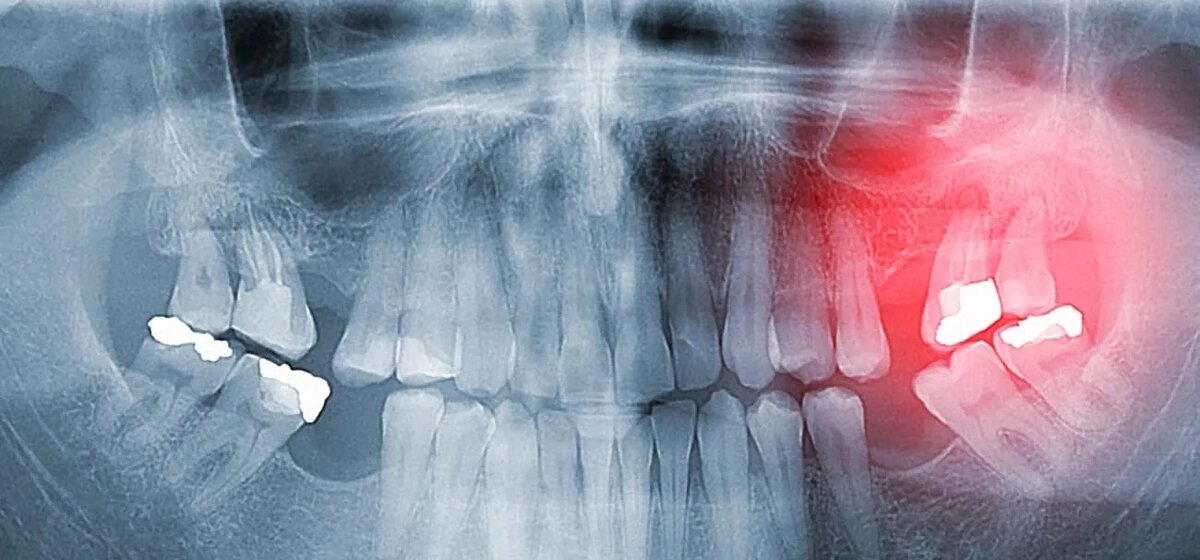

Фото взято из открытых источников

Периодонтит — это серьезное воспалительное заболевание тканей, окружающих корень зуба, которое может привести к серьезным осложнениям, вплоть до потери зуба. Болезнь возникает из-за инфицирования периодонта — структуры, соединяющей зуб с челюстной костью. Без своевременного лечения воспалительный процесс может привести к разрушению костной ткани и распространению инфекции на соседние структуры.

Периодонтит может проявляться в острой и хронической форме. Острая форма сопровождается интенсивной пульсирующей болью, которая усиливается при накусывании. Может наблюдаться отек десны, покраснение и общее недомогание. В некоторых случаях повышается температура тела.

Хронический периодонтит развивается постепенно, часто без выраженных болевых ощущений. Возможны неприятные ощущения при жевании, периодическое появление свищевых ходов с выделением гноя, а также подвижность зуба. Со временем болезнь приводит к разрушению окружающей кости и образованию кист или гранулем.